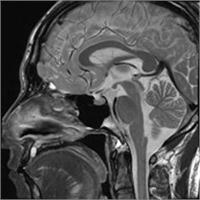

AIR Recon DL画像の一例

脳